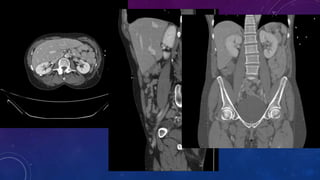

MULTIPLE GALL STONES

GB AND RIGHT RENAL CALCULI.